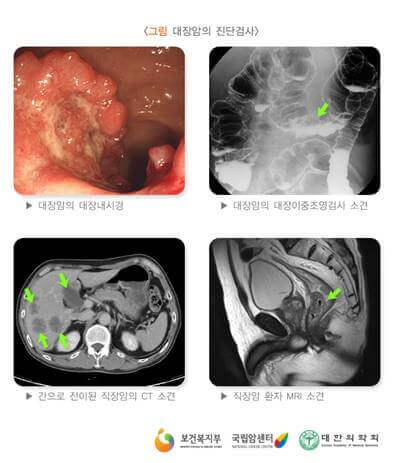

대장암 초기증상 검사

대장암은 대장내시경검사, 결장경검사 및 대변 기반 검사를통해 발견할 수 있어요. 대장내시경검사가 가장 철저한 선별검사 방법입니다. 끝에 카메라가 달린 길고 유연한 튜브를 사용하여 전체 결장과 직장을 시각화해요. 폴립이 발견되면 이 내시경이 진행되고 있는 도중에 제거할 수 있답니다.

대장내시경과 유사하게 결장경검사는 유연한 튜브를 사용하여 직장과 결장 하부를 검사해요. 그러나 결장 전체를 볼 수는 없답니다.

대변기반검사는 대장암의 징후일 수 있는 대변의 혈액 또는 DNA 돌연변이를 확인하는 검사입니다.